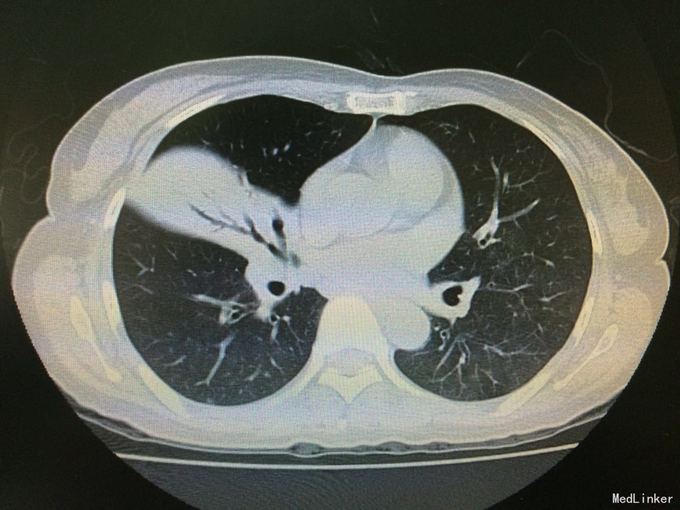

查体:双肺呼吸音粗,双肺底可闻及明显湿性啰音。 辅查:胸部CT示:双肺炎症。CRP66mg/l,ESR105mm/h,PCT0.074ng/ml。血常规、痰涂片及培养阴性。支气管镜示:左支气管见少量白色粘液状分泌物,右侧见中量白色脓性分泌物。支气管进管时患者无明显咽喉刺激反射。